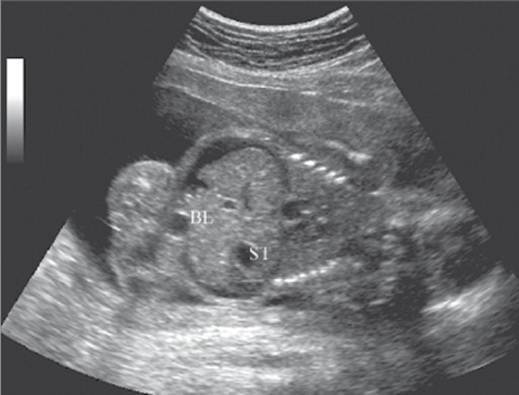

Measurement of incompetent cervix